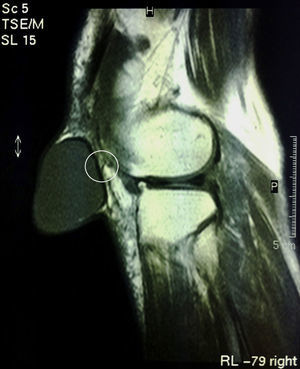

Finalmente, se realizó una resonancia magnética (RM) (fig. 3) que confirmó el diagnóstico de tumoración quística sin poder identificar ninguna comunicación patente con la articulación ni con la bursa prerrotuliana, aunque se pudo reconocer un pequeño pliegue no comunicante en la pared posterior de la misma. La anatomía del resto de la rodilla no presentaba alteraciones salvo las propias relacionadas con la edad de la paciente.

Los quistes sinoviales son entidades habitualmente benignas localizadas fuera de la cápsula articular pero relacionadas anatómicamente con esta por medio de pequeños canales que pueden identificarse permeables u obliterados1,5. En nuestro caso, se identificó un pliegue de la pared posterior del quiste que podría ser la estructura remanente de un canal actualmente obliterado que comunicaba el quiste con la articulación (fig. 3). Los quistes sinoviales se producen por degeneración mucinosa, traumatismos o tumores1. Por cualquiera de estos motivos, ocurre un desplazamiento de líquido sinovial desde regiones de alta a baja presión provocando una progresiva movilización del tejido sinovial y eventualmente la evaginación de este fuera de la cápsula articular2. Una vez que se produce este fenómeno, el líquido puede establecerse o desplazarse desde la articulación al quiste libremente a través de un canal cuya permeabilidad puede ser permanente, episódica o de escasa duración6. El desplazamiento del líquido en uno u otro sentido condiciona que la cavidad aumente o disminuya de tamaño2.